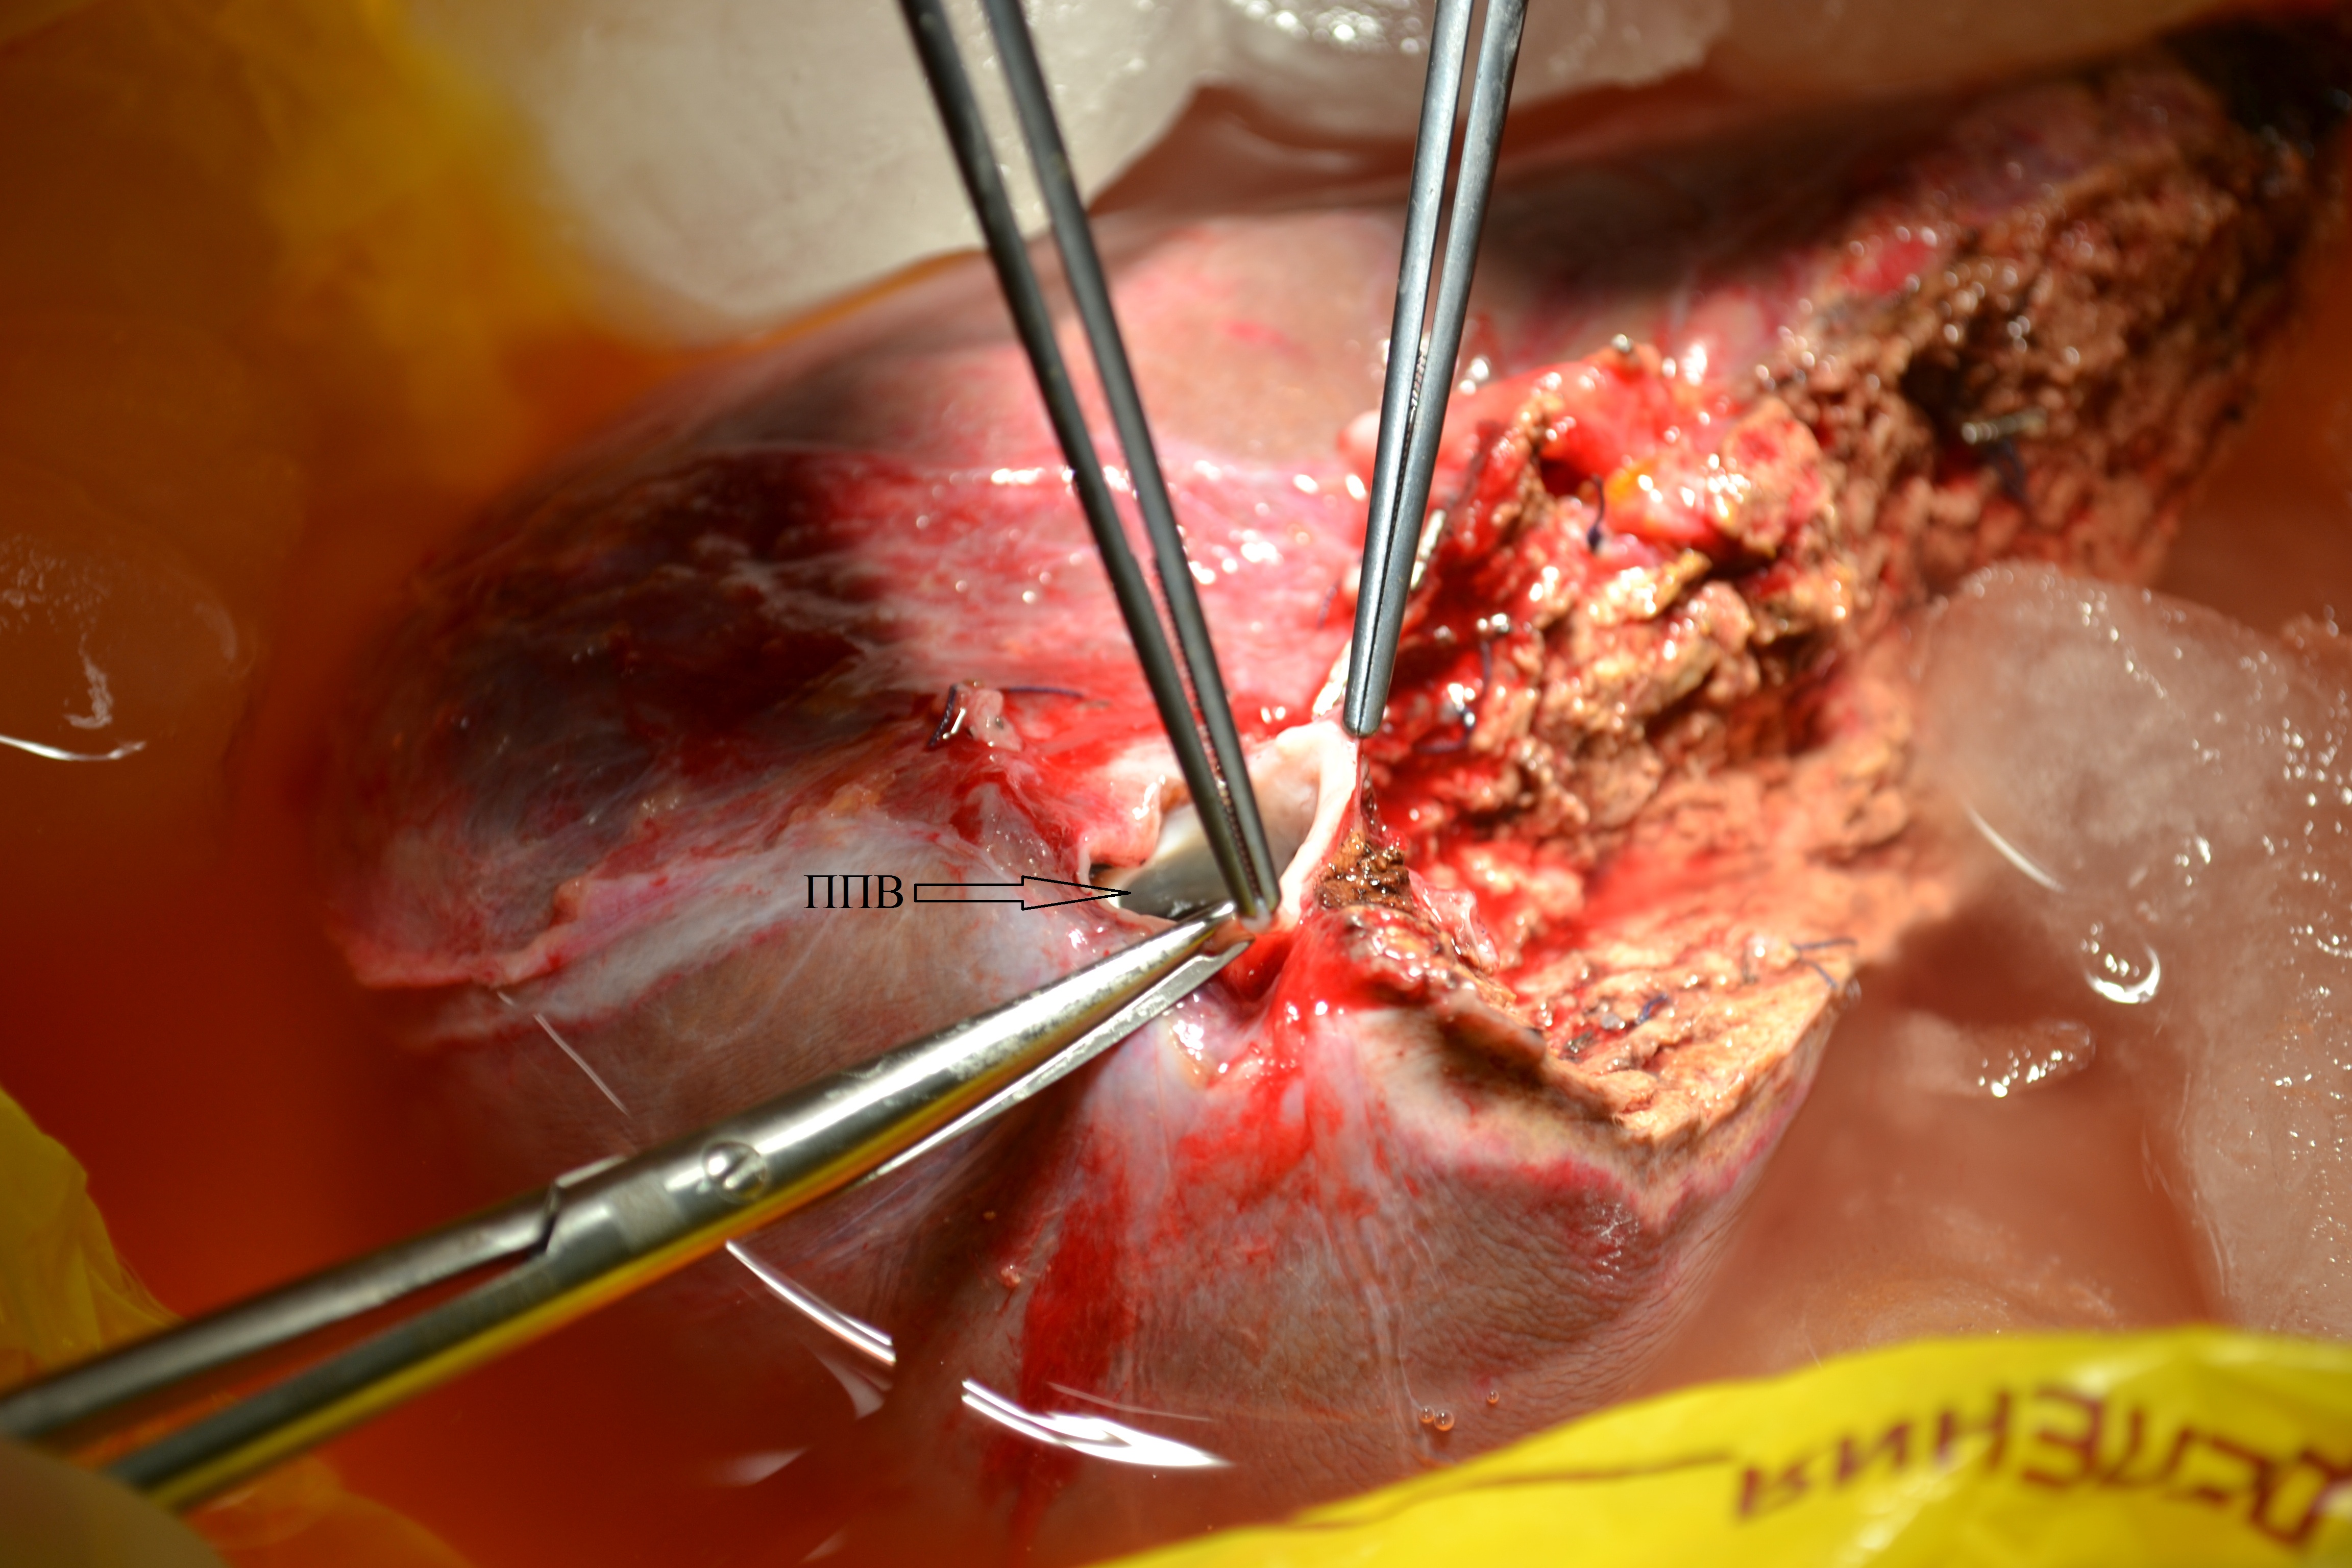

4. Тип А (фото). | |

| Тема | ||

| Тип | Исследовательские инструменты | |

Посмотреть

(2MB)

|

Метаданные ▾ | |